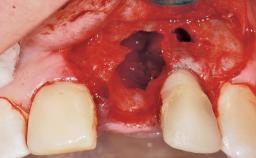

Late Flapless Placement of an Implant in a Maxillary Left Central Incisor Site

A 39-year-old male patient presented with a chief complaint of discomfort and gingival discoloration around his maxillary left central incisor. He was in good general health and was a non-smoker. His past dental history was significant because of the traumatic fracture of tooth 21 in a sporting accident at age 13. Initial dental treatment included endodontic therapy and a full-coverage restoration. The patient became symptomatic 5 years later, when structural failure of the tooth resulted in the dislodgment of the crown. Endodontic retreatment, apical surgery, and post-and-core restoration were performed.

| Soft Tissue Anatomy | Intact | Defective | |

| Bone Volume | Deficient horizontally, requiring prior grafting |